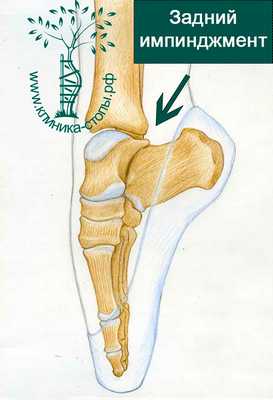

Задний импиджмент синдром

Задний импинджмент синдром голеностопного сустава чаще всего встречается у артистов балета. Это связано с хождением на пальцах стопы, а в этом положении происходит избыточное сгибание в голеностопном суставе, и, соответственно, травма задних отделов голеностопного сустава.

Задний импинджмент часто связно с анатомическими особенностями строения голеностопа и травмами. Задний тип импинджмента характерен в основном для балетных танцоров. Ведь во время этого танца человек вынужден много ходить на кончиках пальцев, что приводит к сильному сгибанию голеностопного сустава в задней части и, как следствие, к травматизации.